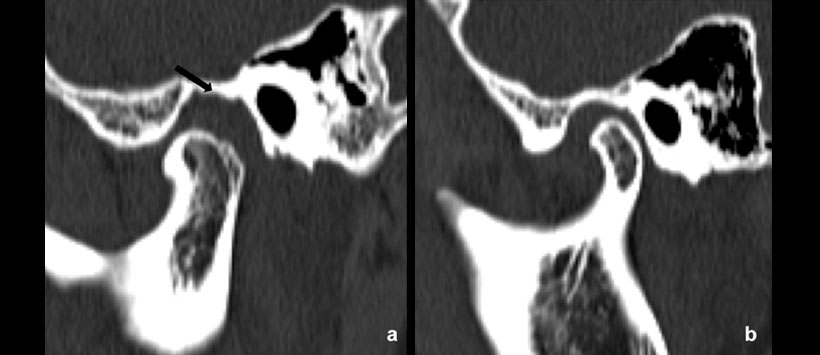

Figura 8: Tomografía Computarizada (TC) en la que se aprecia aumento del espacio articular del lado afectado con erosión severa de la cavidad glenoidea (flecha negra).